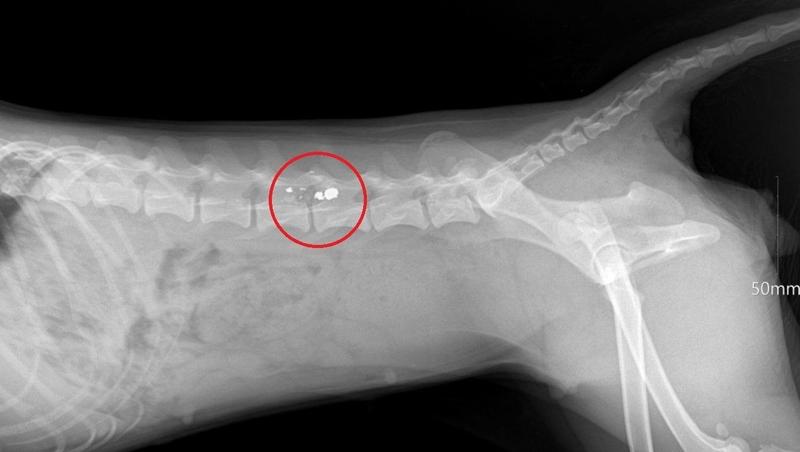

Ветеринары, осмотревшие животное, диагностировали паралич тазовых конечностей.

Дробь попала в позвоночник